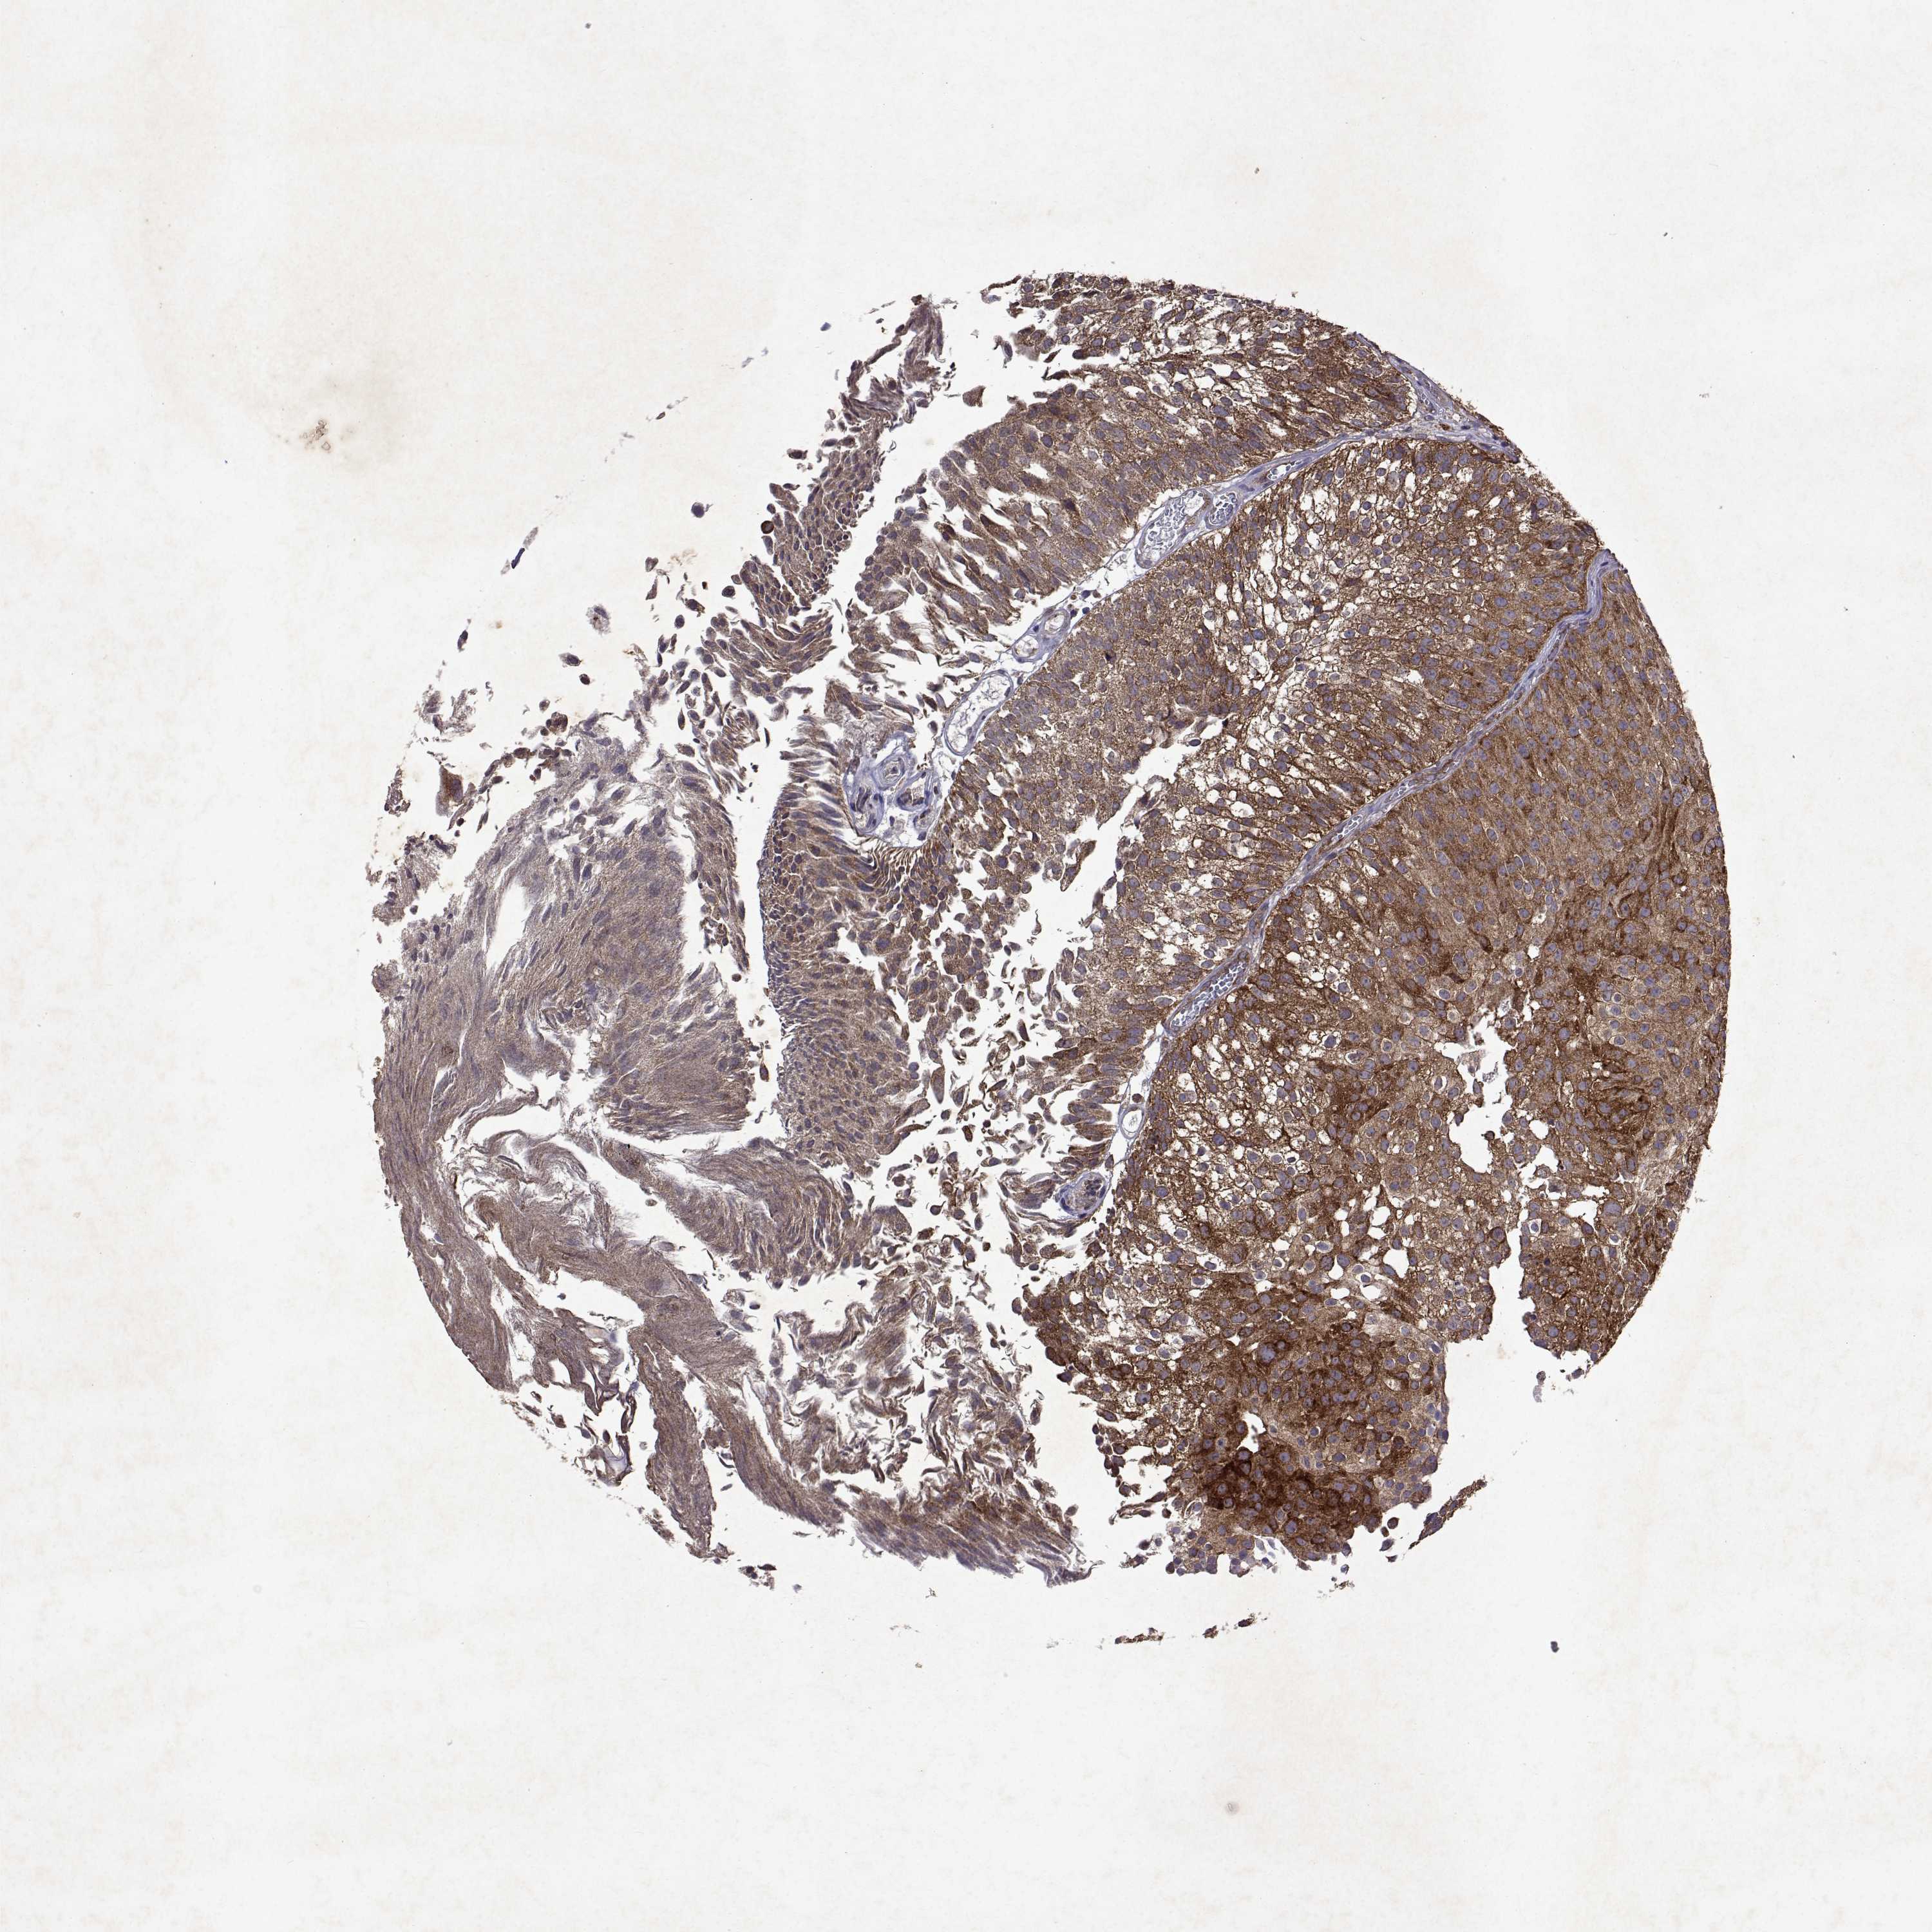

UROTHELIAL CANCER - Protein expressioni

A mouse-over function shows sample information and annotation data. Click on an image to view it in a full screen mode. Samples can be filtered based on level of antibody staining by selecting one or several of the following categories: high, medium, low and not detected. The assay and annotation is described here.

Note that samples used for immunohistochemistry by the Human Protein Atlas do not correspond to samples in the TCGA dataset.

Antibody stainingi

Antibody staining in the annotated cell types in the current human tissue is reported as not detected, low, medium, or high, based on conventional immunohistochemistry profiling in selected tissues. This score is based on the combination of the staining intensity and fraction of stained cells.

Each image is clickable and will lead to virtual microscopy that enables deeper exploration of all samples and also displays staining intensity scores, fraction scores and subcellular localization as well as patient and tissue information for each sample.

Antibody HPA051181

Antibody HPA061454

Antibody CAB069406

Urothelial carcinoma, High grade

Urothelial carcinoma, Low grade

Urothelial carcinoma, NOS